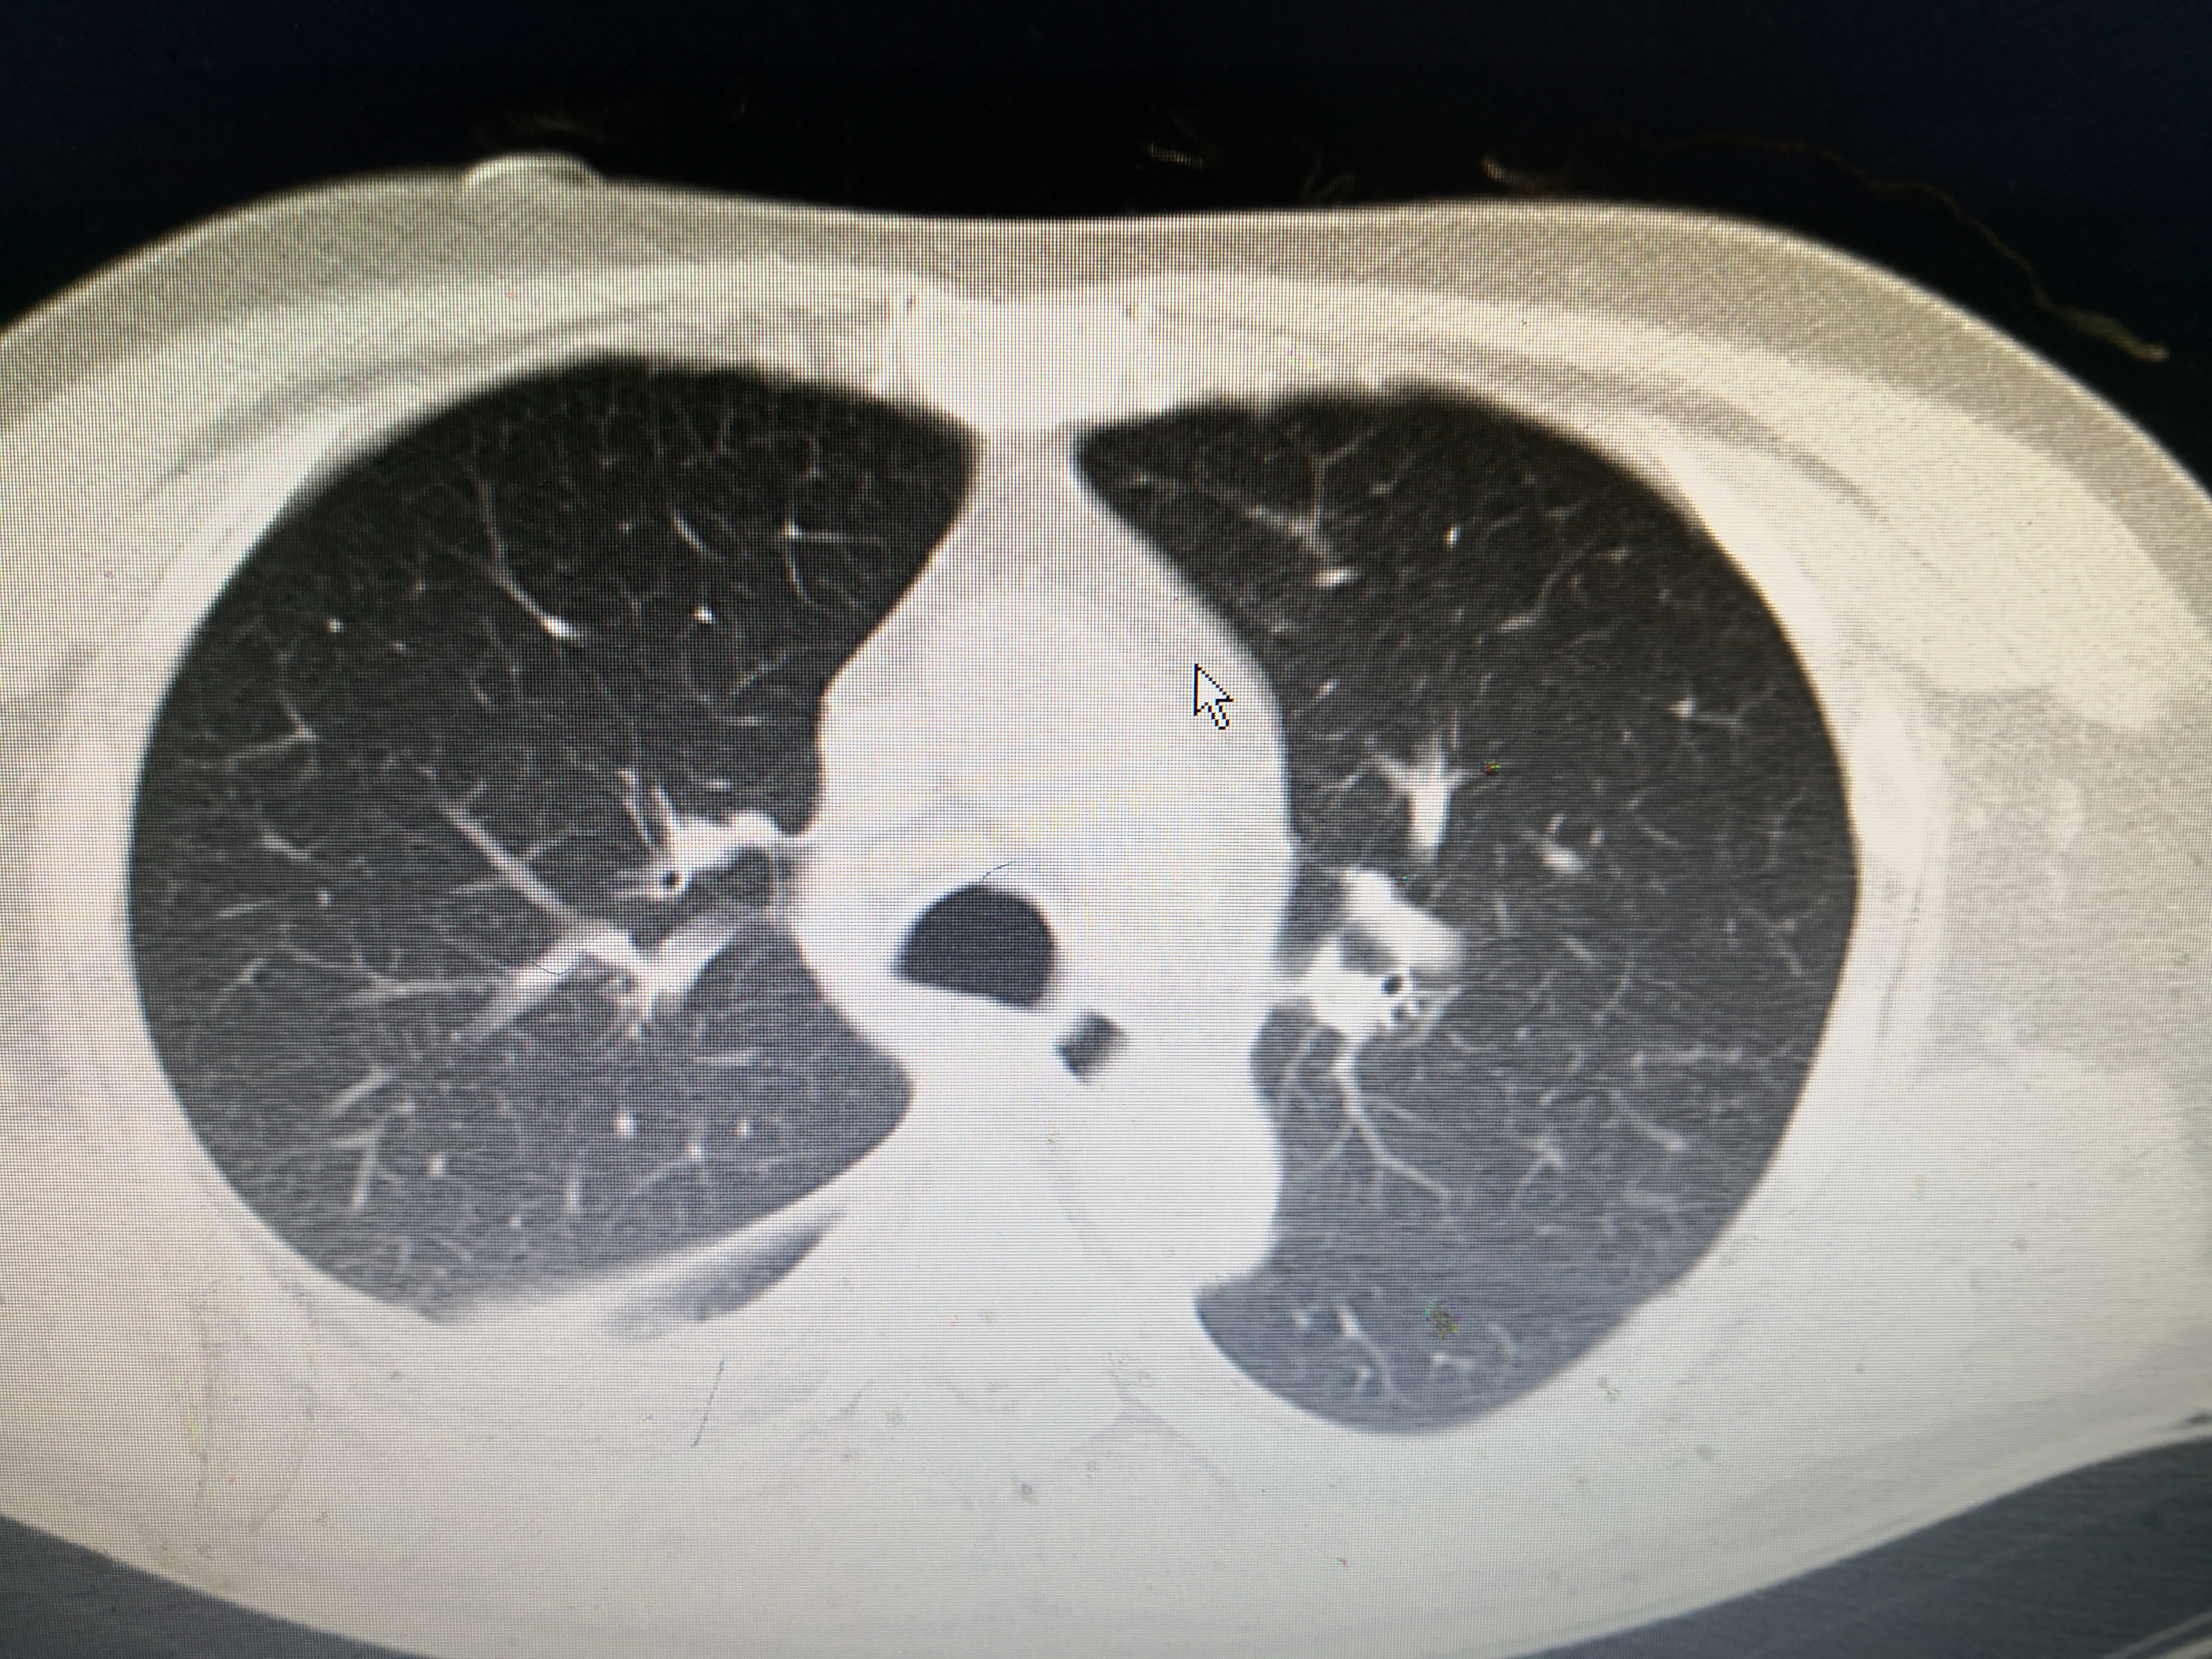

下面这个患者就是近期从西城院区转过来的发热,大片肺炎患者。患者男,55岁,因发热3天到西城院区就诊,体温最高41℃,伴有畏寒、乏力、纳差,咳嗽少痰,伴有顽固性呃逆,没有新冠肺炎流行病学史,但是CT提示右肺大片炎症,在发热门诊隔离抗炎,经两次筛查阴性,但是抗炎效果不佳,仍有高热,转到这边急诊二病区抗炎治疗。

该患者没有既往病史,没有新冠流行病学史,没有用药史,有典型的发热、咳嗽症状,CT提示右肺炎症。